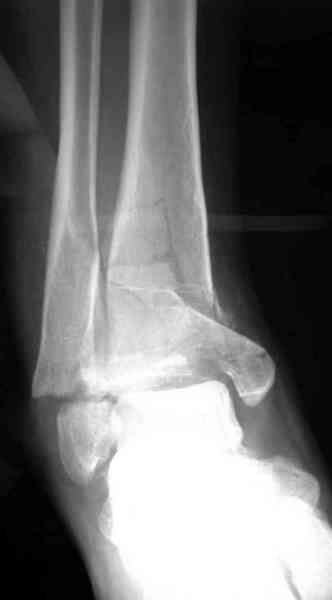

Первичная пластина или интрамедуллярный фиксатор на малоберцовую зависит от характера перелома, косые и многооскольчатые пластинами, а поперечных можно интрамедуллярными фиксаторами. Восстановленная длина малоберцовой служит ориентиром и помогает определению высоты большеберцовой во время восстановления.

Переломы пилона сопровождаются ударом со сминанием в метафизарной части большеберцовой, то есть со значительной потерей костного объема.

При репозиции суставных поверхностей образуются полости в метафизарных отделах, без заполнения их

структуральными элементами невозможно предохраниться от посттравматической деформации. Латеральная колонна удерживается малоберцовой поэтому голень деформируется в варус.

Здесь выставлена пара случаев перелома пилона, оба

случая леченные этапным наружным фиксатором.